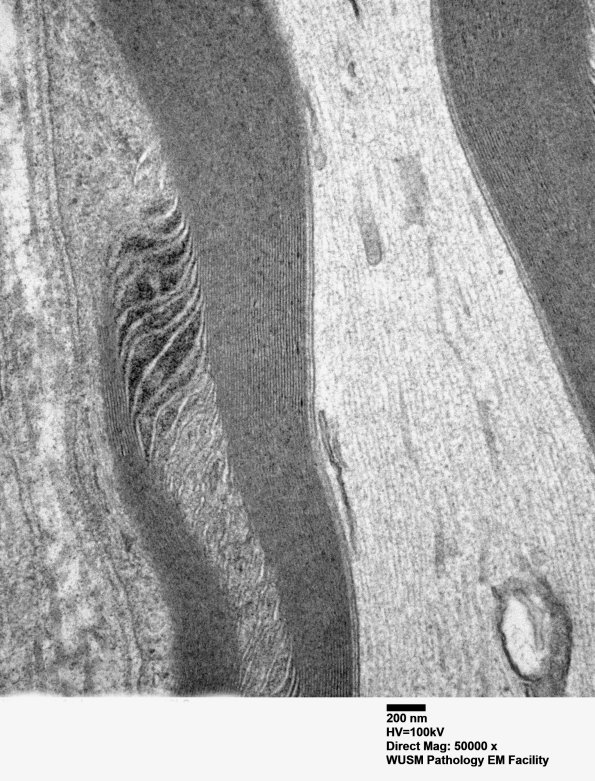

Washington University Experience | PERIPHERAL NEUROPATHY | 3 NORMAL MYELIN & SCHWANN CELLS | 3 Schmidt-Lanterman Clefts | 2A5 W24-3671 Anders G (Case 2) Sural_059 - Copy

Higher magnification of image #2A4. (electron micrograph)